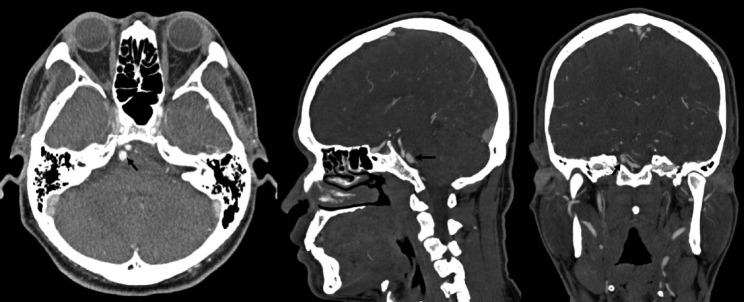

The Anterior Inferior Cerebellar Artery-Posterior Inferior Cerebellar Artery (AICA-PICA) common trunk is a rare variant of cerebral posterior circulation in which a single vessel originating from either the basilar or vertebral arteries supplies both cerebellum and brainstem territories. We present the first case of an unruptured right AICA-PICA aneurysm treated with flow diversion using a Shield-enhanced pipeline endovascular device (PED, VANTAGE Embolization Device with Shield Technology, Medtronic, Canada). We expand on this anatomic variant and review the relevant literature. A 39-year-old man presented to our treatment center with vertigo and right hypoacusis. The initial head CT/CTA was negative, but a 4-month follow-up MRI revealed a 9 mm fusiform dissecting aneurysm of the right AICA. The patient underwent a repeat head CTA and cerebral angiogram, which demonstrated the presence of an aneurysm on the proximal portion of an AICA-PICA anatomical variant. This was treated with an endovascular approach that included flow diversion via a PED equipped with Shield Technology. The patient's post-procedure period was uneventful, and he was discharged home after two days with an intact neurological status. The patient is still asymptomatic after a 7-month follow-up, with MR angiogram evidence of stable aneurysm obliteration and no ischemic lesions. Aneurysms of the AICA-PICA common trunk variants have a high morbidity risk due to the importance and extent of the territory vascularized by a single vessel. Endovascular treatment with flow diversion proved to be both safe and effective in obliterating unruptured cases.

小脑前下动脉-小脑后下动脉(AICA-PICA)共同干是大脑后循环的一种罕见变异,即由基底动脉或椎动脉的单一血管供应小脑和脑干区域。我们介绍了首例使用盾牌增强管道内血管装置(PED,加拿大美敦力公司的带盾牌技术的 VANTAGE 栓塞装置)进行血流分流治疗的未破裂右侧 AICA-PICA 动脉瘤病例。我们对这一解剖变异进行了详细阐述,并回顾了相关文献。一名 39 岁的男子因眩晕和右侧听力减退来到我们的治疗中心。最初的头部 CT/CTA 检查结果为阴性,但 4 个月后的磁共振成像检查发现右侧 AICA 有一个 9 毫米的纺锤形剥离动脉瘤。患者再次接受了头部CTA和脑血管造影检查,结果显示在AICA-PICA解剖变异的近端存在动脉瘤。患者接受了血管内治疗,包括通过装有盾牌技术的 PED 进行血流分流。患者术后恢复顺利,两天后出院回家,神经状况良好。经过 7 个月的随访,患者仍无症状,磁共振血管造影显示动脉瘤闭塞稳定,无缺血性病变。AICA-PICA 共干变异动脉瘤的发病风险很高,这是因为单根血管血管化区域的重要性和范围。事实证明,在未破裂的病例中,使用血流分流的血管内治疗既安全又有效。